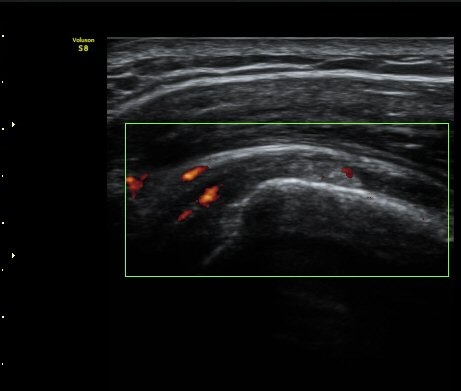

ÆÄ¿öµµÇ÷¯°Ë»ç¿¡¼­ ±Ø»ó°Ç°ú Á¡¾×³¶ÁÖÀ§¿¡¼­ ¼ö¾×Àú·ù°¡ °üÂûµÈ´Ù(±×¸² 6, 7).